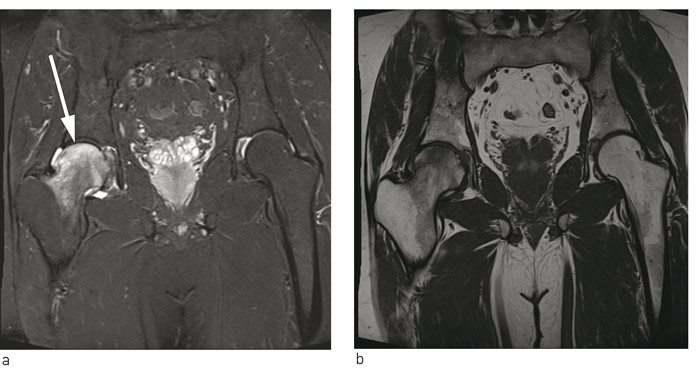

Røntgen viste en liten ujevnhet lateralt i høyre caput femoris av usikker betydning. MR-bildene viste på høyre side et diffust benmargsødem i caput og collum femoris (fig 1). Etter kontrast var det opptak i samme område og ubetydelig væske i leddet. Det var ingen tegn til subkondral fraktur.

På MR-bilder er benmargsødem karakterisert av diffust utbredte forandringer i form av væskelignende signal fra benmarg med nedsatt signalintensitet på T1-vektede bilder og økt signalintensitet på væskesensitive sekvenser, f.eks. T2-vektede bilder med fettsuppresjon eller «short tau inversion recovery»-sekvens (STIR) (1).

På bakgrunn av flere kasuistikker hvor man beskrev mulig effekt av peroral bisfosfonatbehandling ved benmargsødemsyndrom, startet vi med alendronat 70 mg en gang i uken (9). Pasienten ble fulgt opp med regelmessige telefonkonsultasjoner, og både smerter og funksjonsnivå bedret seg gradvis. Ved kontroll seks måneder etter symptomdebut var han smertefri og kunne belaste benet fullt. Ny MR-undersøkelse viste full tilbakegang av benmargsødemet i caput femoris, men noe ødem i acetabulum. Etter ytterligere tre måneder var MR bekken og hofteledd helt normalisert (fig 2). Bentetthetsmåling viste da T-skår –2,6, og –2,1 i henholdsvis høyre og venstre hofte. Videre oppfølging av endokrinolog viste vedvarende lett forhøyet PTH-nivå uten at det ble funnet noen sikker årsak til dette.